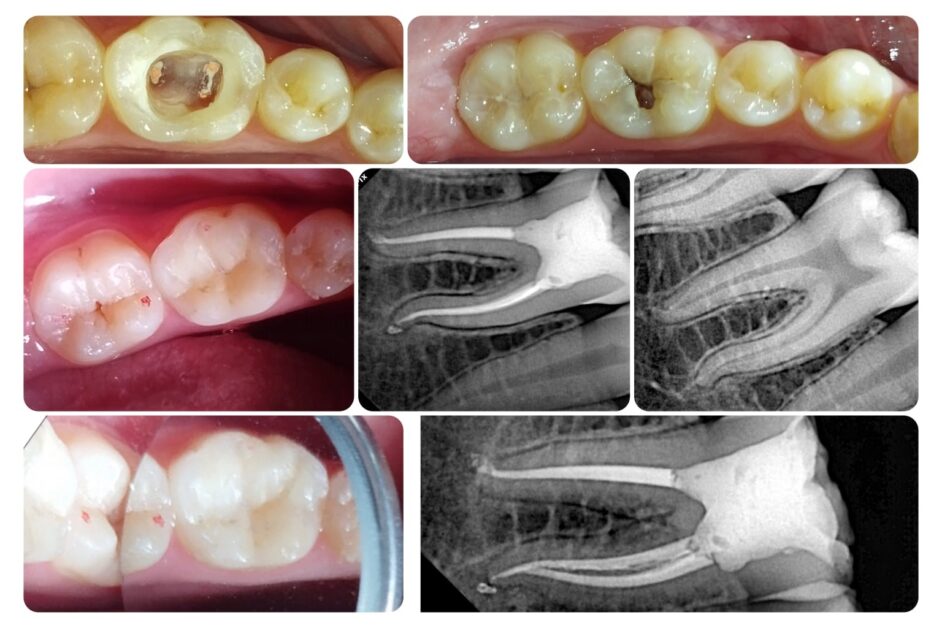

Root Canal Treatment (RCT)

With a focus on painless RCT procedures, Dr. Mohajer uses modern rotary instruments to clean infected canals thoroughly. His advanced methods preserve the natural tooth structure, minimizing discomfort and ensuring long-term success.